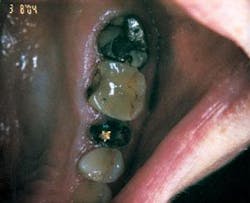

Upon examination, it was determined that Teeth Nos. 13, 14, 18, and 30 were indicated for root canal therapy (Figure 2). Fortunately, Dr. Christian Mangin, an endodontist, was able to accommodate this patient in the limited amount of time available. The remaining posterior teeth had large, carious, fractured amalgams. The maxillary anterior teeth had interproximal caries with crowding.